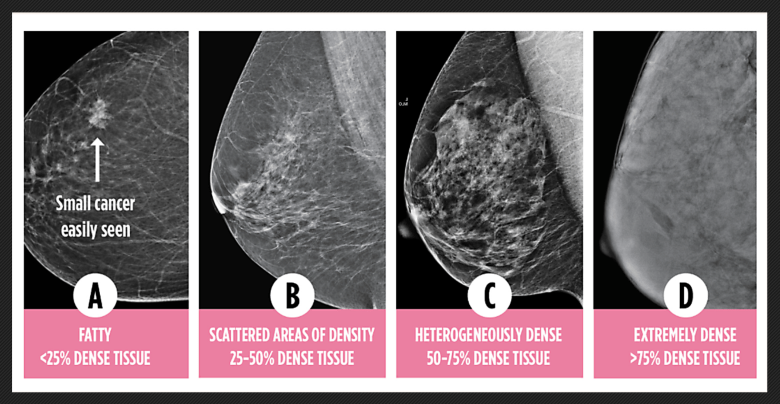

Levels of breast density. Credit: Dense Breasts Canada

Nearly half of all women who have a mammogram are told they have dense breasts. Dense breasts are common but carry two serious risks: they increase the chance of developing breast cancer and they make cancer harder to detect. On a mammogram, dense tissue and cancer both appear white, creating a masking effect. The result? Cancers are often missed until they grow and spread, leading to more aggressive treatment, higher costs, and worse outcomes.